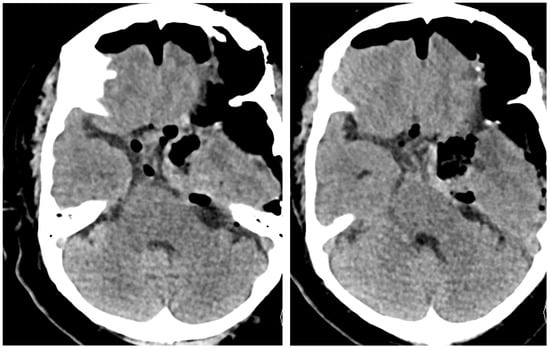

2.1. Case 1

2.2. Case 2